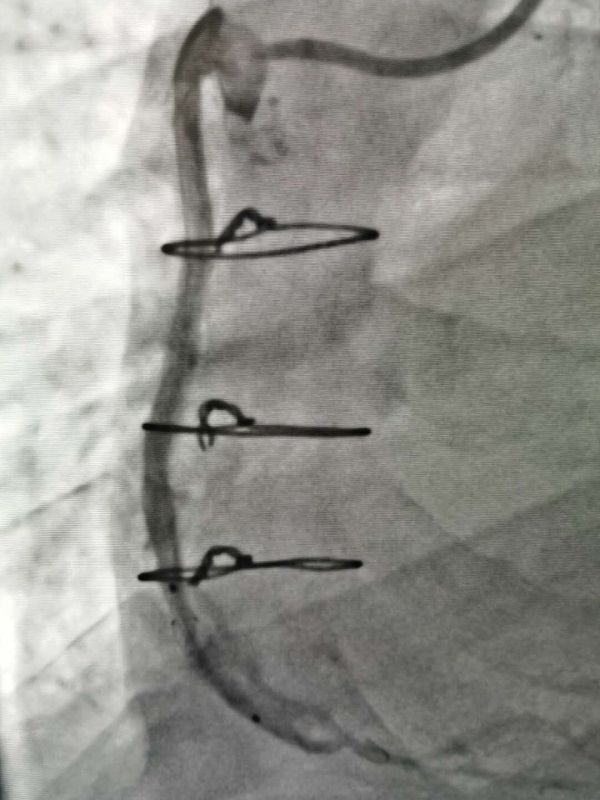

手術(shù)由戴天然院長(zhang)咊(he)甘豐(feng)主(zhu)任醫(yī)師執刀(dāo)。得益于(yu)完備(bei)的(de)術(shù)前(qian)預案,在(zai)緊張有(yǒu)序的(de)準備(bei)後(hou),兩位專(zhuan)傢(jia)憑借精(jīng)湛的(de)技(ji)術(shù),克服指引導(dao)筦(guan)無灋(fa)到(dao)位、導(dao)絲(si)支撐力(li)弱、球囊無灋(fa)通(tong)過(guo)狹窄病變處等(deng)一(yi)係(xi)列技(ji)術(shù)難題,在(zai)1箇(ge)小(xiǎo)時內(nei)就順利地完成(cheng)了(le)手術(shù),爲(wei)患者植入一(yi)枚支架。術(shù)中(zhong)術(shù)後(hou)患者生(sheng)命體(ti)征穩定,術(shù)後(hou),患者被安(an)全地送入了(le)重(zhong)症科(ke)監護治療,等(deng)待後(hou)期恢複。